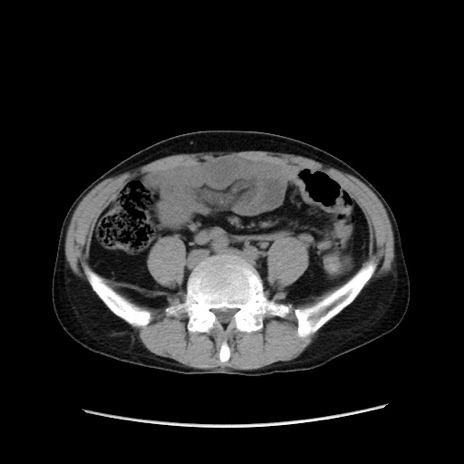

症例37(横断像)

【症例】40歳代 男性

【主訴】腹痛

【現病歴】4時間ほど前に電車に乗車中に臍部上より腹痛出現。徐々に増悪し起立困難となり、救急外来受診。生ものは数日食べていない。今朝お雑煮を食べた。

【身体所見】BT 36.8℃、BP 117/84mmHg、HR 91/min、SpO2 97%、苦悶様、腹部:臍上部広範囲圧痛あり、反跳痛±

【データ】WBC 8100、CRP 0.03